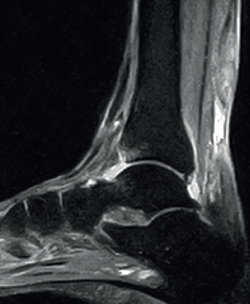

The normal Achilles tendon is observed as a hypointense structure in both T1- and T2-weighted sequences(33)(Figure 3). In the sagittal plane its margins are parallel, and in the axial plane its distal portion presents an anterior concave margin towards the calcaneus over most of its course. The thickness is similar along its trajectory, and a minimum amount of fluid is observed at retrocalcaneal level (fluid surrounding the tendon is pathological)(34).

Figure 3. Magnetic resonance imaging view of ankle (T1 sequencing). Sagittal view showing a normal tendon.

With regard to the pathological patterns of the Achilles tendon (Table 2), MRI visualizes tendinosis as a loss of the normal form of the tendon, with fusiform thickening. Loss of the anterior flattening can be observed in sagittal sequences, together with convexity of the anterior surface of the tendon in axial sequences. We can also observe hyperintense zones in the central part of the tendon in both T1- and T2-weighted sequences, with tendon neovascularization(34). It must be taken into account that signs of Achilles tendinosis can be found in asymptomatic individuals(35).